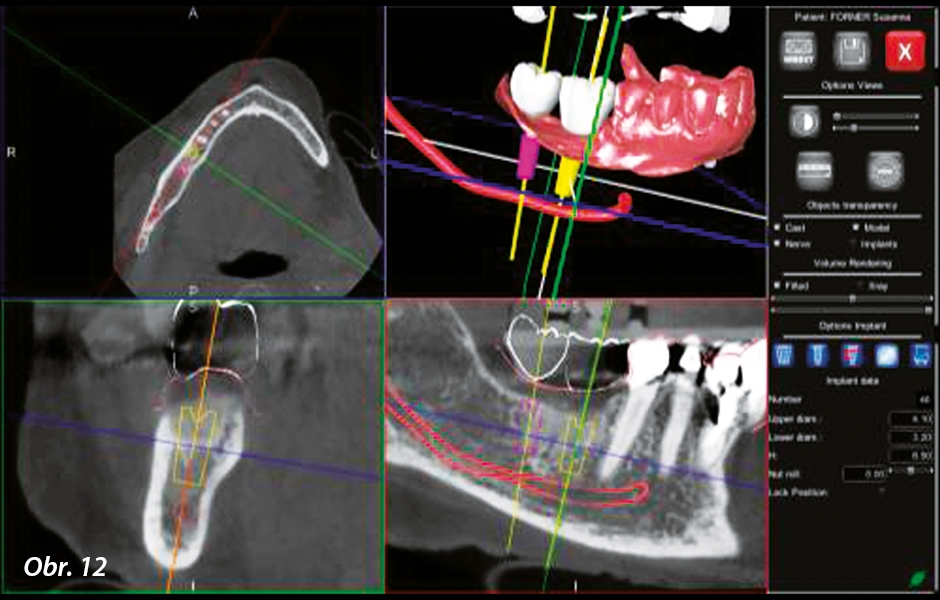

Modely zubních oblouků získané z otisků jsou skenovány pomocí 3D skeneru, který generuje trojrozměrné soubory STL (obr. 5). Získané soubory jsou zpracovány v modelovacím softwaru, který umožňuje virtuální vytvoření diagnostického voskového modelu. To se děje při výběru oblasti určené k restaurování, v tomto případě oblasti zubů 46 a 47, a na tomto místě jsou umístěny zuby vybrané z knihovny virtuální anatomie (obr. 6 a 7). Software se stará o optimalizaci vztahů se sousedními a antagonálními prvky (obr. 8). V tomto okamžiku jsou dva objemy, z nichž jeden pochází z CT a druhý z digitalizace modelů, zarovnány a zobrazeny v plánovacím softwaru (obr. 9–11).